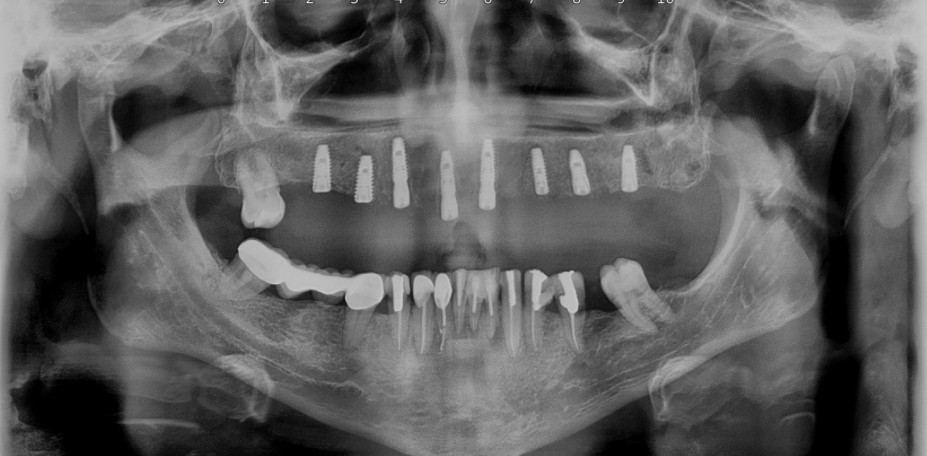

لمینیت سرامیکی دندان(طراحی لبخند) کامپوزیت ونیر دندان (طراحی لبخند) ایمپلنت و کلیه جراحی های تخصصی فک و صورت توسط جراح و متخصص دهان و فک و صورت کلیه خدمات دندانپزشکی به صورت تخصصی با بالاترین کیفیت توسط بهترین دندانپزشکان و در محیط کاملا vip

کلینیک دندانپزشکی دندانپزشکی زیبایی مرکز کامپوزیت دندان مرکز لمینت دندان مرکز ارتودنسی دندان دندانپزشکی کودکان دکتر ارتودنسی کودکان دندانپزشکی اطفال دکتر دندانپزشک متخصص ایمپلنت دندانپزشکی شبانه روزی عصب کشی جراح دندانپزشک جراح دندان عقل جراح لثه جراحی لثه با لیزر متخصص درمان ریشه دندان متخصص لمینت دندان متخصص ارتودنسی ایمپلنت فوری اصلاح طرح لبخند بلیچینگ دندان دندانپزشکی بدون درد کاشت دندان متخصص پروتز دندان ایمپلنت دیجیتال لیفت لثه با لیزر دندانپزشکی با لیزر دکتر دندانساز ایمپلنت اقساطی مشاهده بیشتر